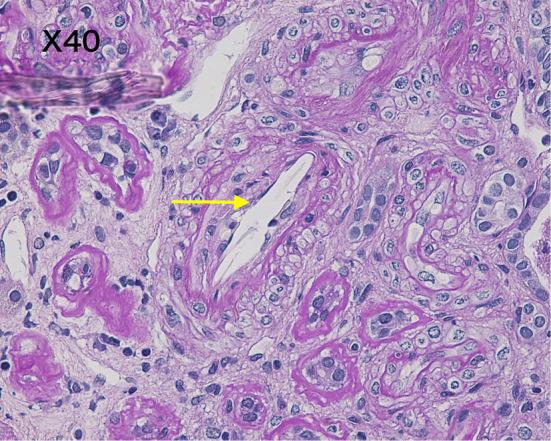

Spontaneous Cholesterol Crystal Embolism and Aortic Plaques.

Intern Med. 2021 Jun 15;60(12):1981-1982. doi: 10.2169/internalmedicine.6511-20. Epub 2021 Jan 15.

DOI:10.2169/internalmedicine.6511-20

PMID:33456045